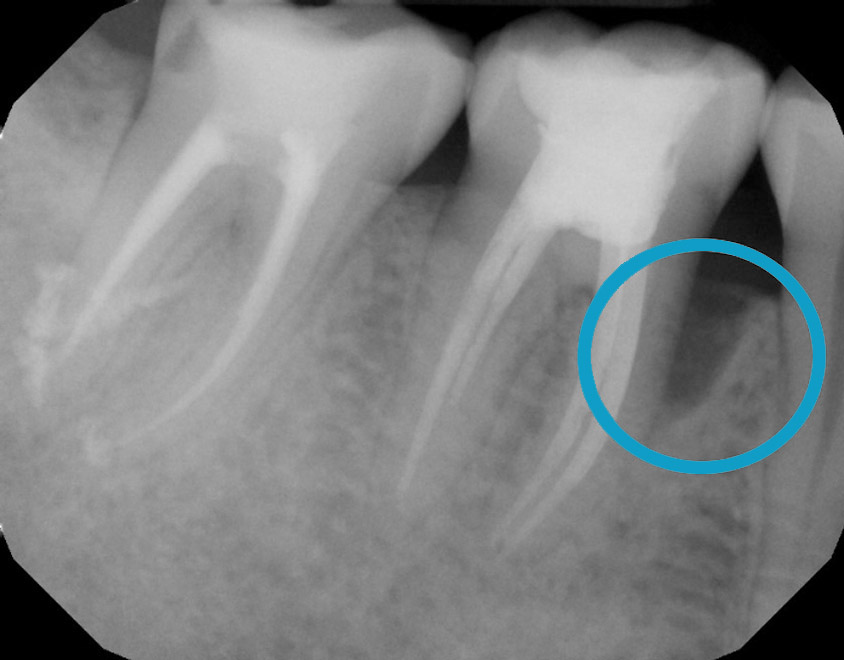

LANAP :

Treat severe gum disease and help the bone grow

One year after treatment, the bone has grown completely to a healthy level. It is all your own natural bone without the need for bone grafting.